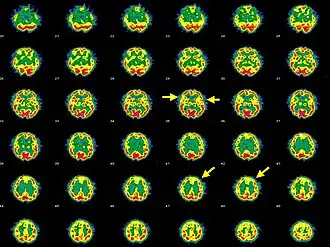

Een psychose is een psychiatrisch toestandsbeeld waarbij de patiënt gedurende een zekere periode het contact met de werkelijkheid geheel of gedeeltelijk kwijt is.

Psychosen worden doorgaans behandeld met antipsychotica die sommige neurotransmitters in de hersenen beïnvloeden. Ze staan bekend om de hinderlijke bijwerkingen die de motoriek storen, energie wegnemen, emoties afvlakken en initiatief wegnemen. Gebrek aan therapietrouw kan daardoor vaak een probleem zijn bij de behandeling van een psychose. De nieuwste middelen zouden minder van deze bijverschijnselen vertonen.